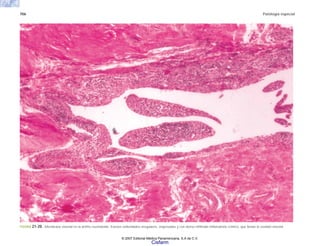

tura, o una herida en la guerra, o el encuentro con un

mágico-religioso de la enfermedad. En algunos casos la